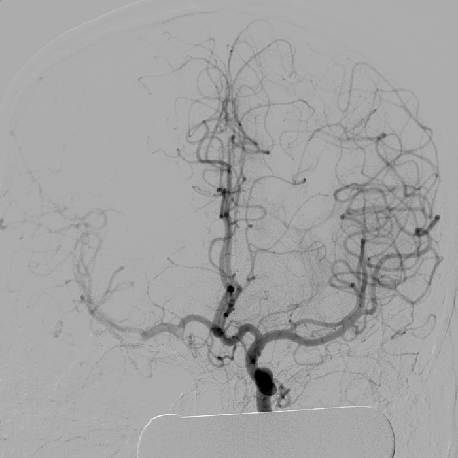

2014-9-29 DSA